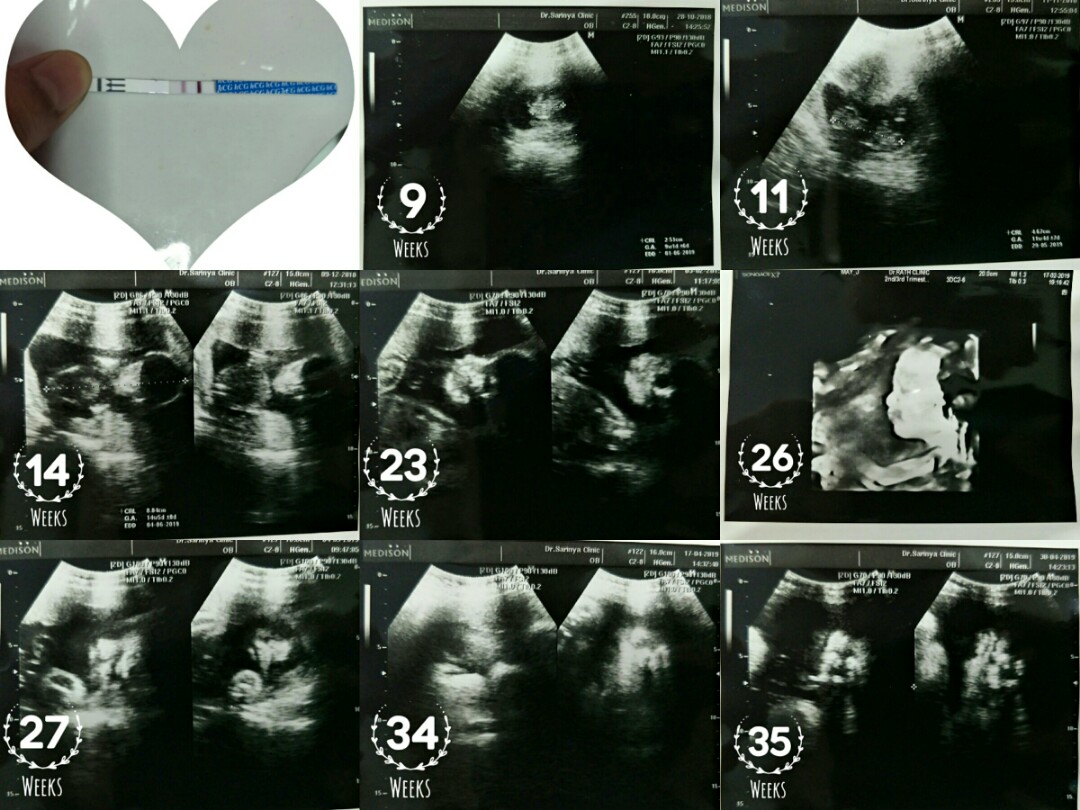

ของเราค่ะ